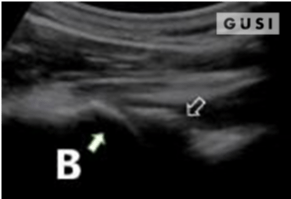

During the 2018 World Taekwondo Junior Championships in Hammamet, Tunisia, a 17-year-old male junior Taekwondo athlete took a fall, landing on his right shoulder. He exhibited a markedly limited range of motion in the affected shoulder and experienced intense pain, leading to suspicions of a dislocation.

A pre-reduction ultrasound (A) of the right shoulder showed a pronounced gap between the humeral head (indicated by a solid arrow) and the glenoid (marked by an open arrow), suggesting an anterior dislocation. Following a shoulder reduction procedure, a post-reduction ultrasound (B) verified the successful realignment of the glenohumeral joint (solid arrow pointing to the humeral head and open arrow to the glenoid).

After the procedure, the athlete displayed a considerably improved range of motion in his right shoulder and his pain levels diminished significantly.